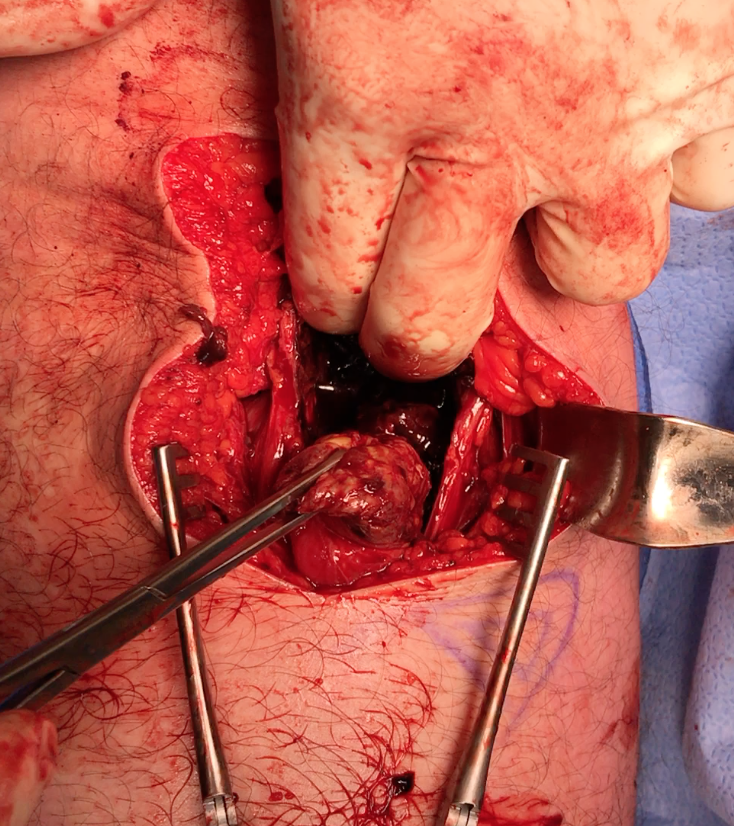

Sciatic nerve with blue vessiloops

Prepare allograft

- tendo achilles

- 9 x 20 mm bone block

- drill to 10 x 25 mm tunnel using ACL instruments

- ensure that beath pin does not advance

- secure with 7 x 20 mm screw, bone typically very strong

Ischial tuberosity exposed, then achilles bone block secured with screw